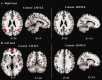

Mesial temporal lobe epilepsy (MTLE) is the most frequent form of focal epilepsy. At rest, there is evidence that brain abnormalities in MTLE are not limited to the epileptogenic region, but extend throughout the whole brain. It is also well established that MTLE patients suffer from episodic memory deficits. Thus, we investigated the relation between the functional connectivity seen at rest in fMRI and episodic memory impairments in MTLE. We focused on resting state BOLD activity and evaluated whether functional connectivity (FC) differences emerge from MTL seeds in left and right MTLE groups, compared with healthy controls. Results revealed significant FC reductions in both patient groups, localized in angular gyri, thalami, posterior cingulum and medial frontal cortex. We found that the FC between the left non-pathologic MTL and the medial frontal cortex was positively correlated with the delayed recall score of a non-verbal memory test in right MTLE patients, suggesting potential adaptive changes to preserve this memory function. In contrast, we observed a negative correlation between a verbal memory test and the FC between the left pathologic MTL and posterior cingulum in left MTLE patients, suggesting potential functional maladaptative changes in the pathologic hemisphere. Overall, the present study provides some indication that left MTLE may be more impairing than right MTLE patients to normative functional connectivity. Our data also indicates that the pattern of extra-temporal FC may vary as a function of episodic memory material and each hemisphere's capacity for cognitive reorganization.